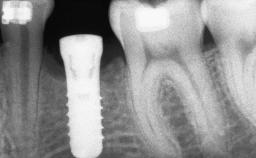

A 45-year-old woman with a completely edentulous maxilla was referred to evaluate the possibility of rehabilitation with an implant-supported prosthesis. This patient was healthy and a non-smoker. She had been wearing a maxillary complete denture opposing a natural mandibular dentition since her twenties. This situation had resulted in progressive resorption of the alveolar ridge, repeatedly creating a need for relining the denture. Twenty years later, despite multiple adaptations and the use of “glues” the denture was unstable and causing the patient psychological and functional discomfort.

# of Implants 8

Bone Augmentation Horizontal|Sinus Floor Elevation|Staged|Vertical

Augmentation Materials Autogenous chips|Autogenous block(s)

Bone Volume Deficient vertically or deficient vertically AND horizontally